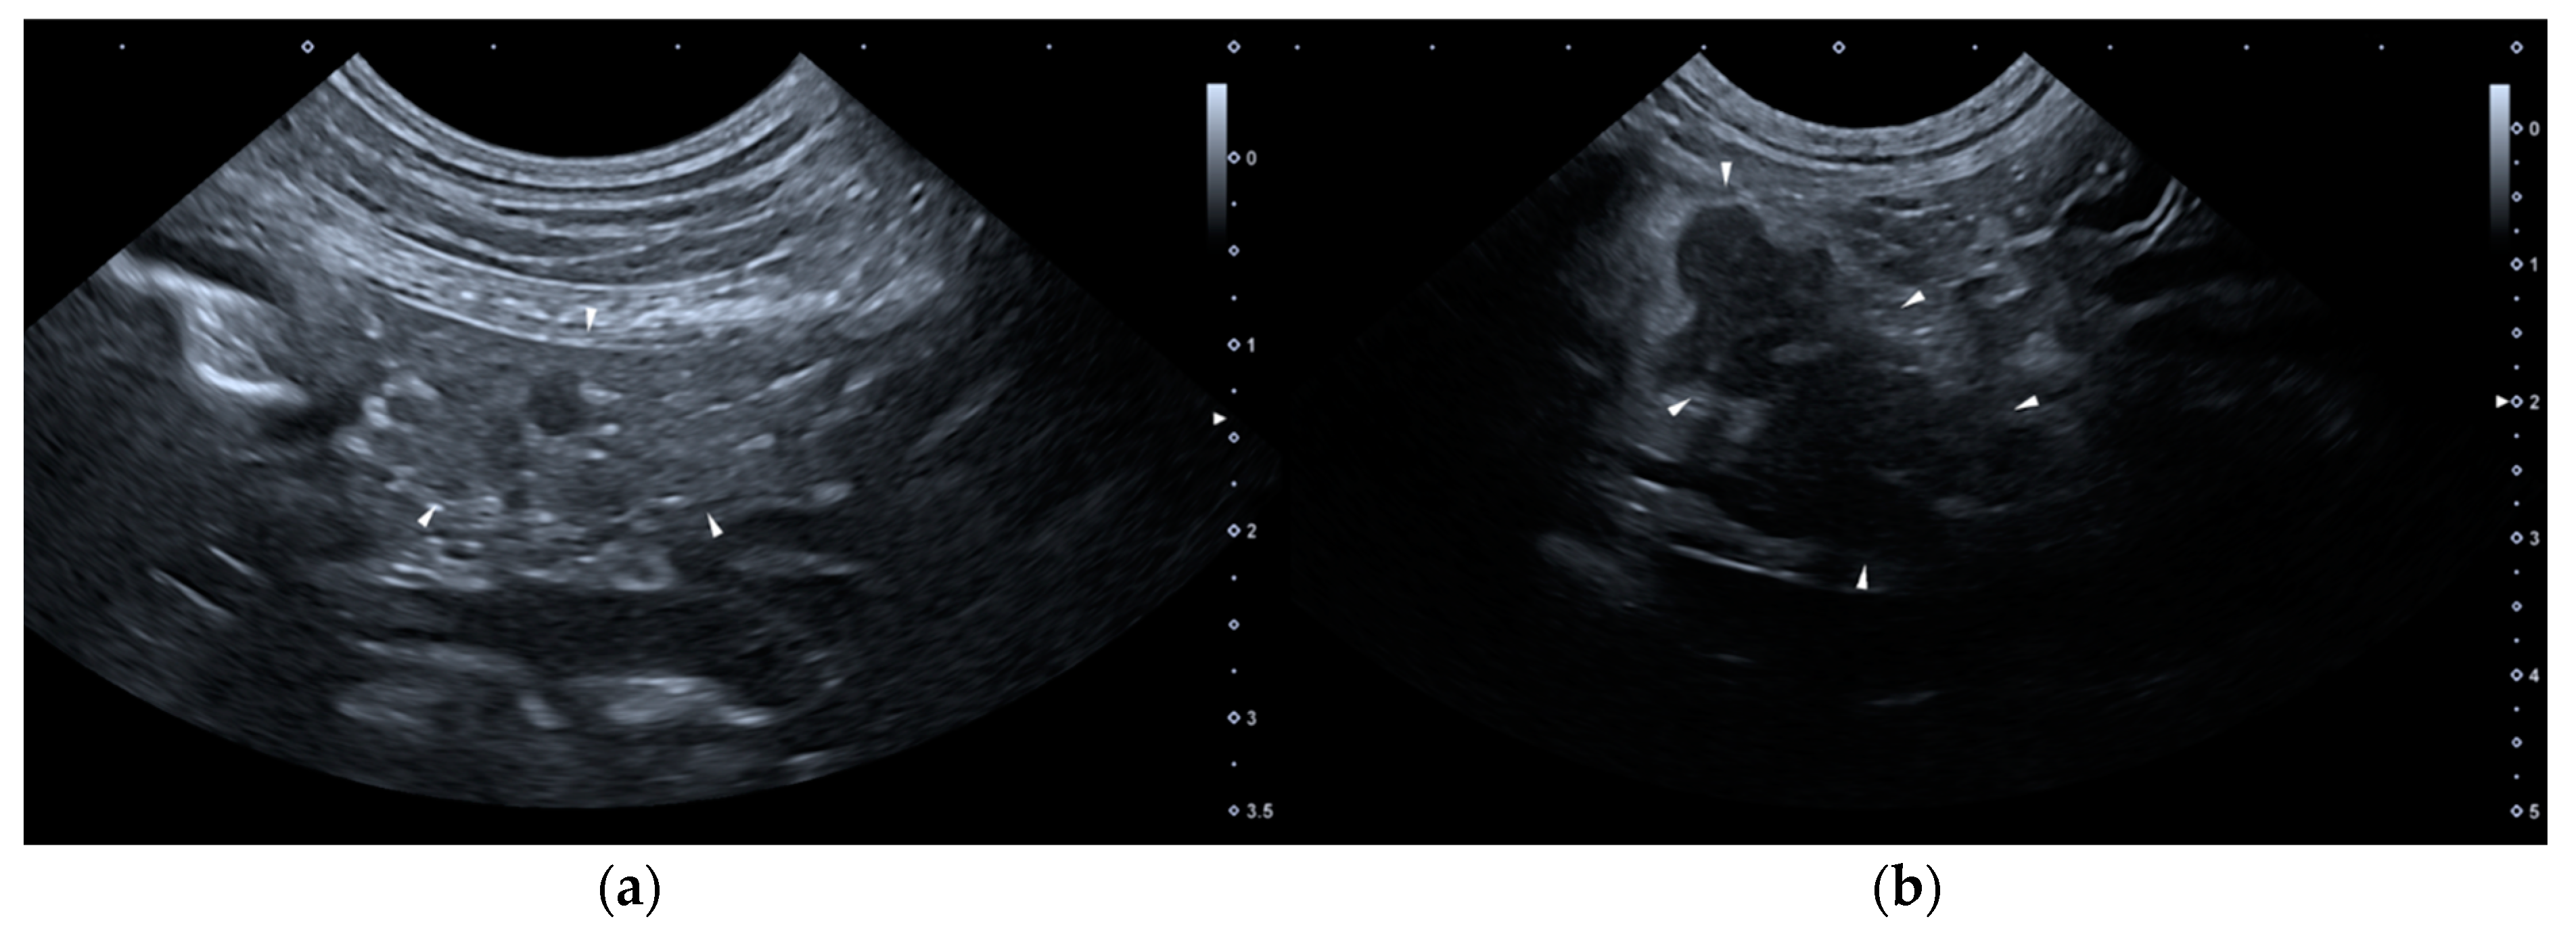

None of the dogs met the required criteria for group B. As for group C (constituted by 14 dogs), on T0 none of the dogs presented HSAs, but two dogs presented two or more PSAs: one of them presented wall thickening and corrugated appearance of duodenum and paralytic ileus, the other one showed wall thickening of the stomach, paralytic ileus and dilation of the common bile duct. Six dogs belonging to group C presented one or more PSAs on T1. Figure 2 shows two ultrasound images of the pancreas of a dog included in the Group C, of T0 and T1, respectively.

Figure 2. Ultrasound images of the right lobe of the pancreas of a dog included in the group C. (a) T0: transverse sonogram of the pancreas, which is normal in size, shape, echogenicity, and echostructure; (b) T1: longitudinal sonogram of the pancreas, which is slightly enlarged and inhomogeneous, hypoechoic and with peripancreatic hyperechoic mesenteric fat. T0: abdominal ultrasound examination performed on the first day of hospitalization; T1: abdominal ultrasound examination performed on the third day of hospitalization.

The dogs belonging to group C showed a clinical presentation consistent with AP and an abnormal result at the SNAP cPL test; however, they had an AUE positive for AP only on T1. We hypothesize that these dogs had not yet developed such extensive damage on T0, which instead manifested itself on T1. This was assumed from the pathophysiology of AP which shows initial acinar cell damage that could subsequently affect the entire organ and also the peritoneal cavity [4]. We hypothesize that at hospital admission, there was microscopic cellular damage in these dogs, which resulted in a release of cPL in the blood circulation which in turn led to the abnormal SNAP cPL test result. In these 14 dogs, the AUE became positive between the first and the second checks as hypothesized by Hecht and Henry, and similarly to humans, where only in 20% of cases the pancreas demonstrates signs of AP on AUE before 48–72 h after symptom onset [15,23].

In group C, on T0 we observed a paralytic ileus associated with the wall thickening of the stomach or duodenum and the corrugated appearance of the duodenum in two dogs, one of which also showed the dilation of common bile duct. Based on their medical records, these two dogs suffered from chronic enteropathy, thus we hypothesized that these ultrasonographic alterations may be related to their underlying pathology. On T1, dogs belonging to group C showed the same type of HSA detected in group A. The dogs belonging to group D did not present ultrasonographic findings suggestive of AP either on T0 or T1. We assume that the pancreatic microscopic damage did not have enough time to hesitate in an ultrasonographic visible macroscopic alteration or that there was limited damage that only affected a small number of pancreatic acinar cells.